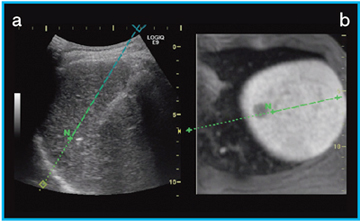

図4 Off-Plane Needle Trackingのライブ画像(a)と造影MRIとのFusionによるNeedle In Plane表示(b)